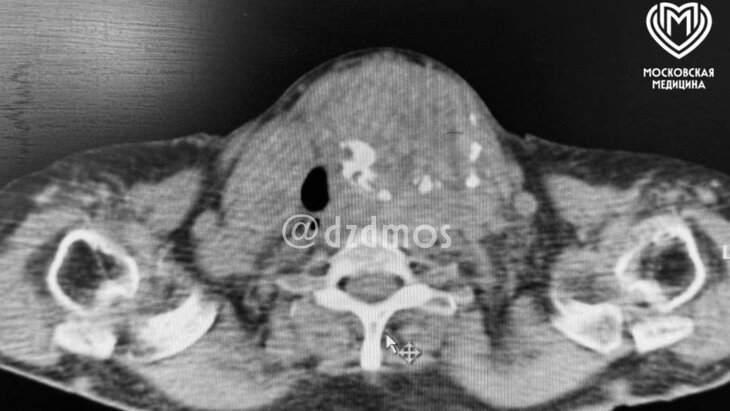

В Москве врачи спасли женщину с гигантским "шаром" в шее, перекрывающим дыхание

У женщины было избыточное содержание углекислого газа в крови (в три раза выше нормы). Врачи провели сложную операцию по удалению щитовидной железы, используя уникальную методику интубации пациента в сознании с помощью фиброскопа. Операция заняла менее двух часов, после чего пациентка почувствовала себя лучше, начала дышать самостоятельно и проходит реабилитацию. Ранее было сообщено, что врачи в Подмосковье успешно провели операцию по удалению атеромы у пенсионерки. После этой операции пациентка призналась, что сожалеет, что не обратилась к хирургам раньше.